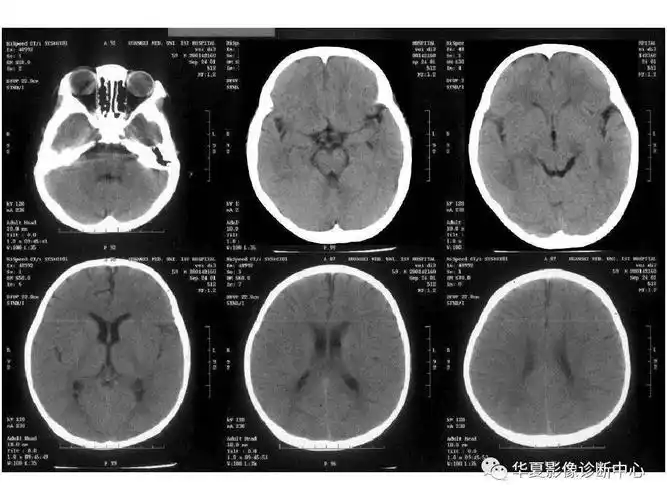

收藏!影像医生必备 | 手把手教你读懂颅脑ct